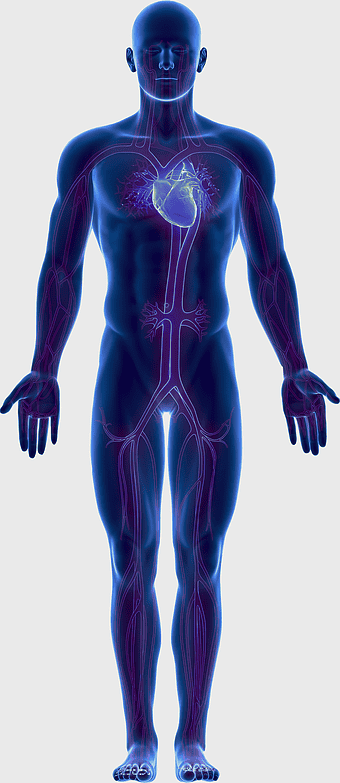

blue human anatomy illustration, human circulatory system diagram, digital human skeleton image, electric blue medical figure, human nervous system visualization, human body organ map, human health care graphic -

1644x2654px

human anatomy illustration, family medicine clinic visuals, blood pressure monitoring, shoulder and hip anatomy, medical diagram of human body, circulatory system depiction, health clinic -

723x1109px